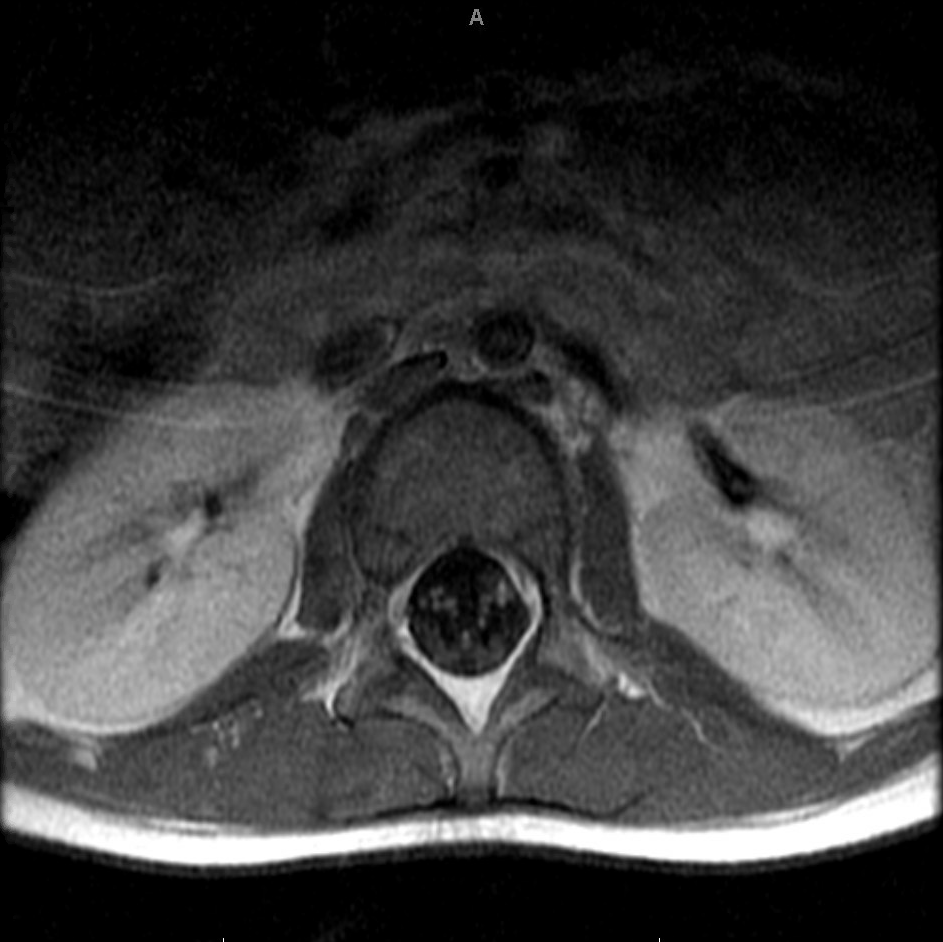

Magnetic resonance imaging (MRI) of the cervical spine and right brachial plexus showed abnormal T2-weighted hyperintensity, most prominent at the craniocervical junction (Figure 1). MRI of the thoracic and lumbar spine showed abnormalities of the cauda equina similar to the cervical spine findings (Figure 2). Brachial plexus MRI findings were normal.

Figure 2. Axial MRI at the level of the conus showing abnormal heterogeneity in the spinal cord.